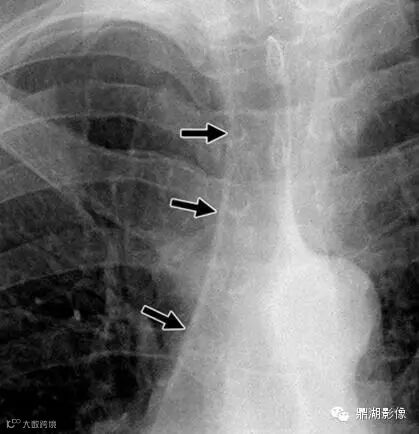

男,35岁(Anterior junction line)

又是一个十分有趣的线——前联合线。它是由双侧前内侧脏层、壁层胸膜对折并夹带少量纵膈脂肪形成的。表现为胸骨上2/3从右上到左下的斜线。线内夹有少量的纵膈脂肪是正常的,纵膈脂肪增多及青少年胸腺可以引起前联合线的增宽如条状。正位片上约40%(25-57%) 可以看到该线,如果胸膜反折线呈斜行而不与X线束方向一致,则前联合线不会显示,心脏、大血管、胸骨、腰椎也会影响前联合线的显示。由于前联合线位于前纵隔,所以前纵隔疾病会使其不显示或曲度异常,如甲状腺、淋巴结、新生物及脂肪增多症。周围肺组织充气过度或过少也可以引起前联合移位。